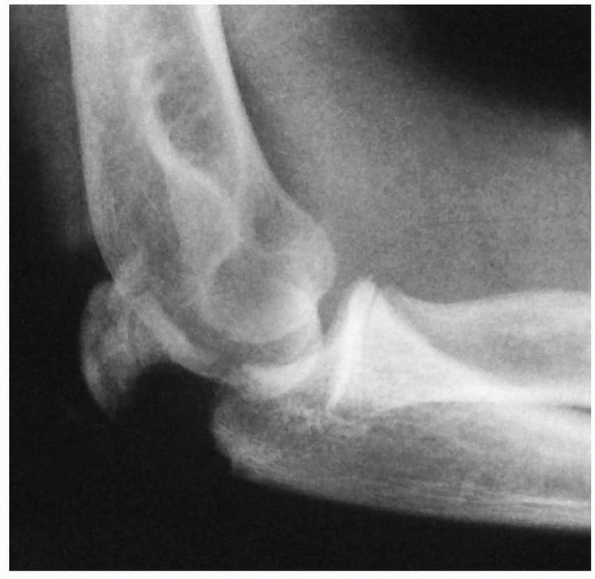

classification based primarily on the mechanism of injury. The two

subclasses of fractures in group I are valgus injuries and those

associated with elbow dislocations. Valgus injuries are subdivided into

three types based on the location of the fracture line (Fig. 11-7).

Fractures associated with an elbow dislocation are subdivided into two

types. The first is based on the original concept proposed by Jeffrey42 that the fracture occurs during spontaneous reduction (Fig. 11-8A). In this case, the radial head lies proximal to the posterior aspect of the joint. The second is based on Newman’s70

concept that the fracture and displacement occur during the process of

dislocation of the elbow. In this type, the radial head lies distal to

the anterior portion of the joint (see Fig. 11-8B).

FIGURE 11-8 Dislocation fracture patterns. A.

Type D: The radial neck is fractured during the process of reduction by the capitellum pressing against the distal lip of the radial head.125 B. Type E: The radial neck is fractured during the process of dislocation by the capitellum pressing against the proximal lip of the radial head.98 C. Radiographs of a radial head that was fractured during the reduction of the dislocation (type D). The radial head (solid arrow) lies posterior to the distal humerus, and the distal portion of the neck (open arrow) is anterior. (Courtesy of Richard E. King, MD.) D. Radiograph of the dislocated elbow in which the fracture of the radial neck occurred during the process of dislocation (type E). |